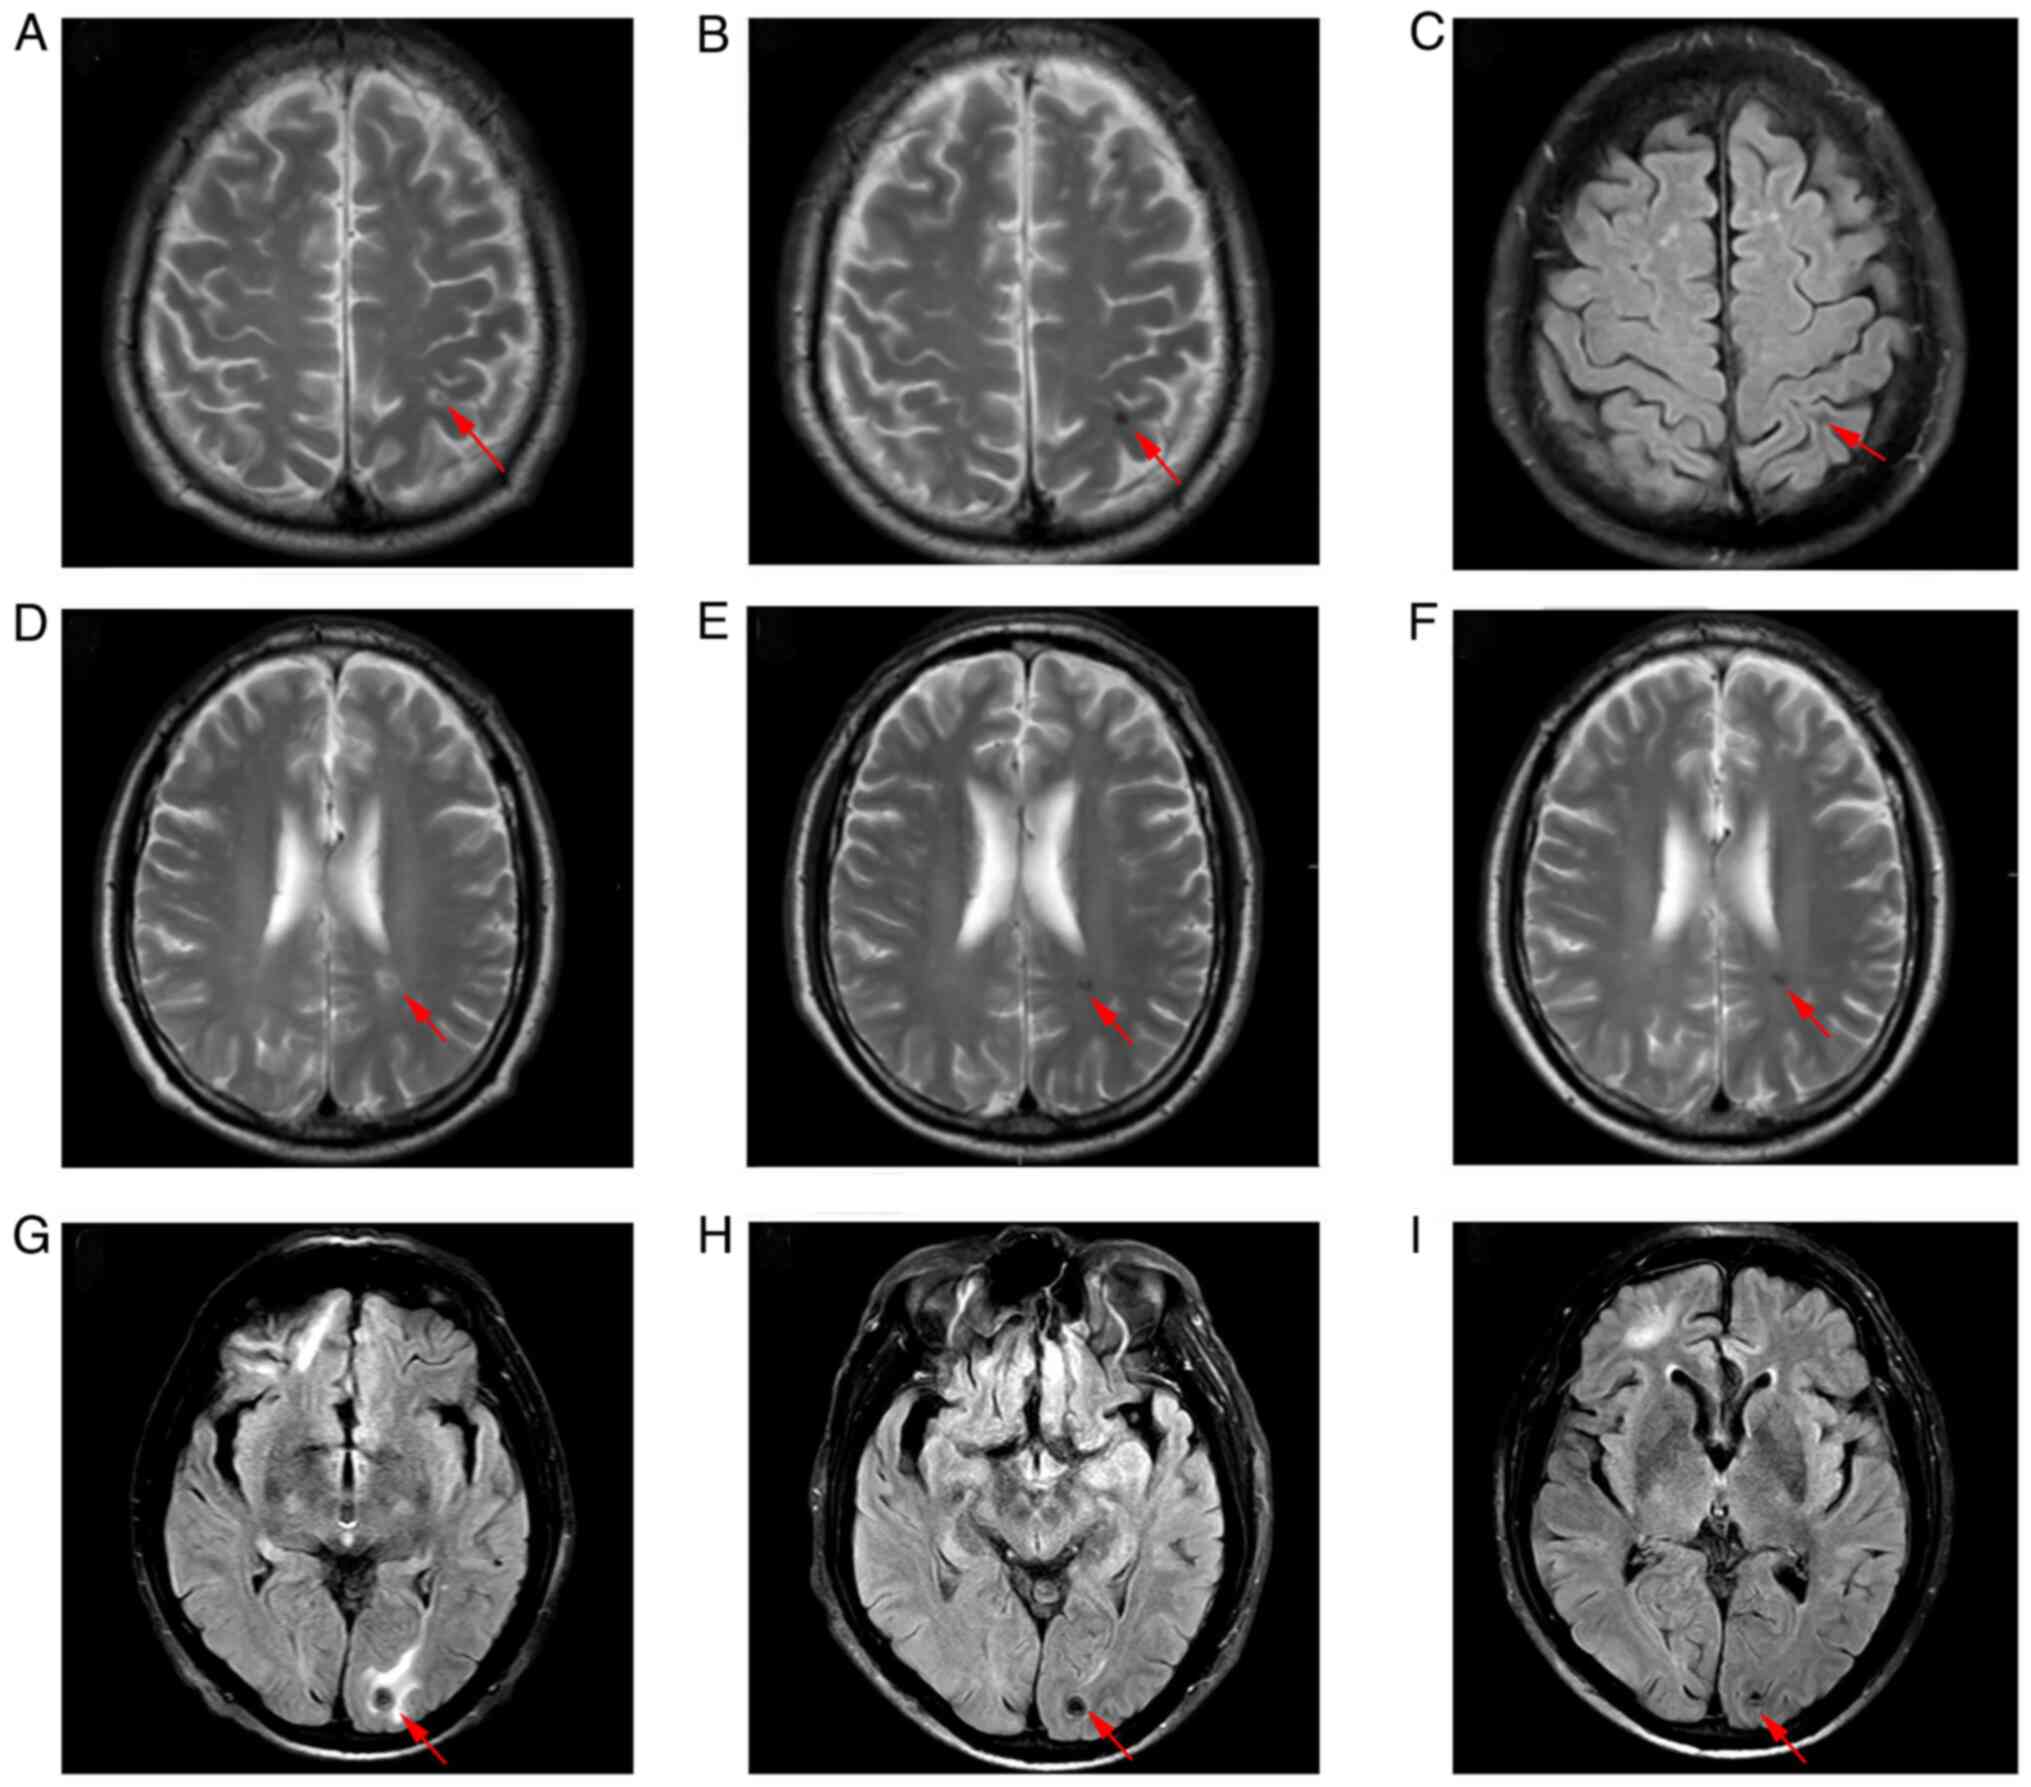

The patient then received chemotherapy with etoposide and cisplatin (EP). Considering the high-volume of lung metastases of the male patient, bleomycin was excluded due to its pulmonary toxicity. HCG levels decreased continuously after each cycle of chemotherapy (Fig. 3), and the patient no longer complained of haemoptysis. However, after two cycles of chemotherapy, a brain MRI revealed new malignant lesions in the (Fig. 4A) left frontal lobe, (Fig. 4D) left ventricle and (Fig. 4G) left occipital lobe. Meanwhile, chest CT showed that some lung lesions had decreased in size, while others had increased in size (Fig. 5A, B, E and F). Stereotactic body radiotherapy (SBRT) of the intracranial lesions was then administered (a dose of 40 Gy delivered in 10 fractions) with concurrent chemotherapy of the third cycle. As the patient suffered from severe bone marrow suppression during chemotherapy, the male patient refused further HDCT or ASCT after six cycles of EP therapy. Although the HCG levels decreased continuously and most of the metastases decreased in size, the treatment was suspended for 6 weeks. Although immunotherapy was recommended, the patient demanded to return to Tibet with oral medication for economic and physical reasons. Comprehensive assessment was then arranged. Laboratory results of the tumour markers showed that HCG was elevated to 572.9 U/l and LDH was 195 U/l. The brain MRI showed stable encephalic lesions with slight reduction in size (Fig. 4A-I). The chest CT revealed that most of the pulmonary lesions were decreasing in size, while others were slightly increasing in size (Fig. 5A-H). The patient returned to Tibet with oral etoposide. Notably, 4 weeks later the patient agreed to receive immunotherapy of sintilimab along with oral etoposide. However, without therapeutic evaluation the condition of the patient deteriorated 2 weeks later. The patient developed respiratory failure accompanied by massive haemoptysis and eventually succumbed 2 days later at home.

Figure 4

Magnetic resonance imaging of the brain. (A) The new lesions (red arrows) in the left frontal lobe, (D) left ventricle and (G) left occipital lobe after two cycles of etoposide and cisplatin chemotherapy. The lesions (red arrows) in the (B and C) left frontal lobe, (E and F) left ventricle and (H and I) left occipital lobe decreased in size after radiotherapy and four cycles of chemotherapy, and remained regressed after six cycles of chemotherapy.